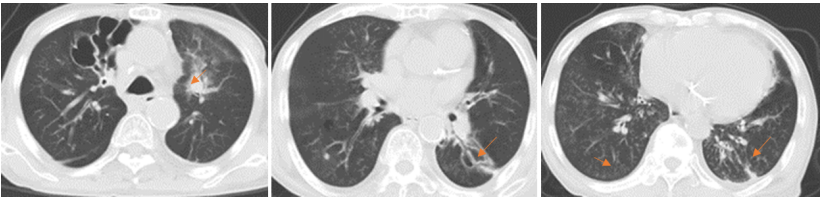

• 胸部CT: 左肺上叶前段团片灶伴支气管狭窄, 双肺炎症、局部实变; 右肺上叶、左肺下叶背段支气管扩张伴感染; 慢支肺气肿; 两肺多发微/小结节; 两侧胸膜增厚粘连(图1)

图片

1  患者胸部CT(2025-03-12)